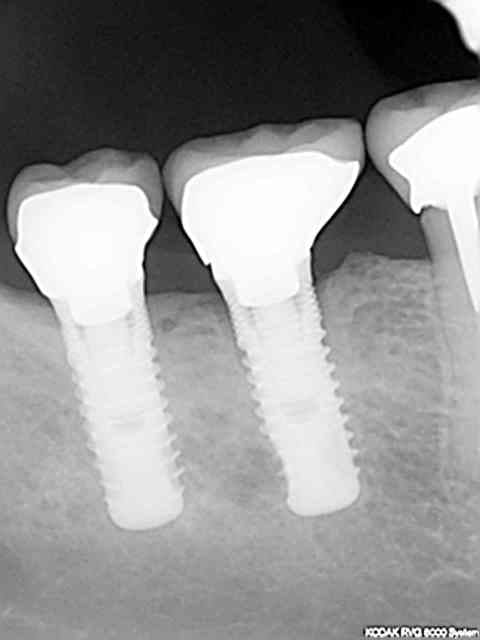

revu la patiente aujourd'hui , fait rvg sur 46 47 pour voir la réponse implantaire , et à postériori tout va bien .

Implant 072008 kcs9ey - Eugenol